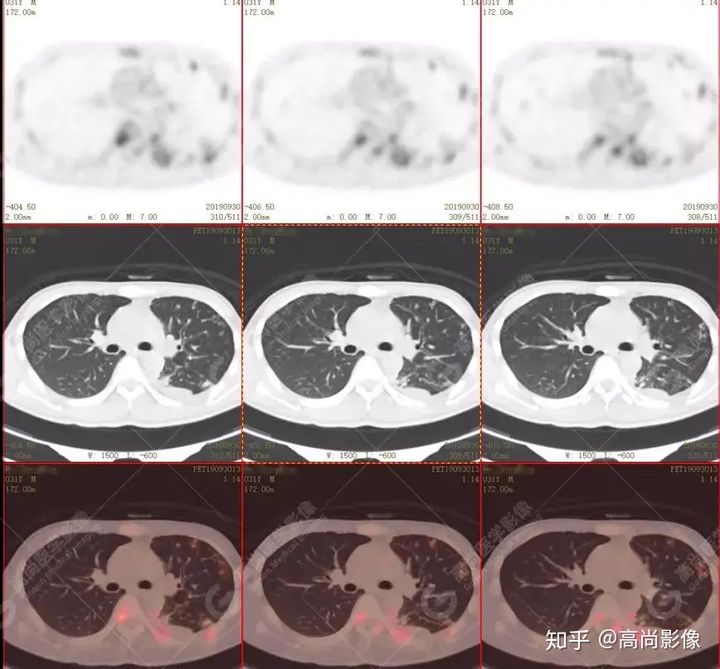

左肺上葉尖后段及下葉背段多發(fā)簇狀斑點狀高代謝灶

左側(cè)胸膜結(jié)節(jié)樣增厚,代謝不同程度增高

【PET/CT提示】雙肺、左側(cè)胸膜多發(fā)結(jié)節(jié)影,全身多處骨質(zhì)破壞,全身多發(fā)淋巴結(jié)腫大,代謝攝取不均勻性增高。

特征:肺部病灶簇狀分布,上葉尖段及下葉背段為著;腫大淋巴結(jié)分布不對稱,無融合、中央有壞死改變,與淋巴瘤、轉(zhuǎn)移瘤等有一定的鑒別診斷意義;